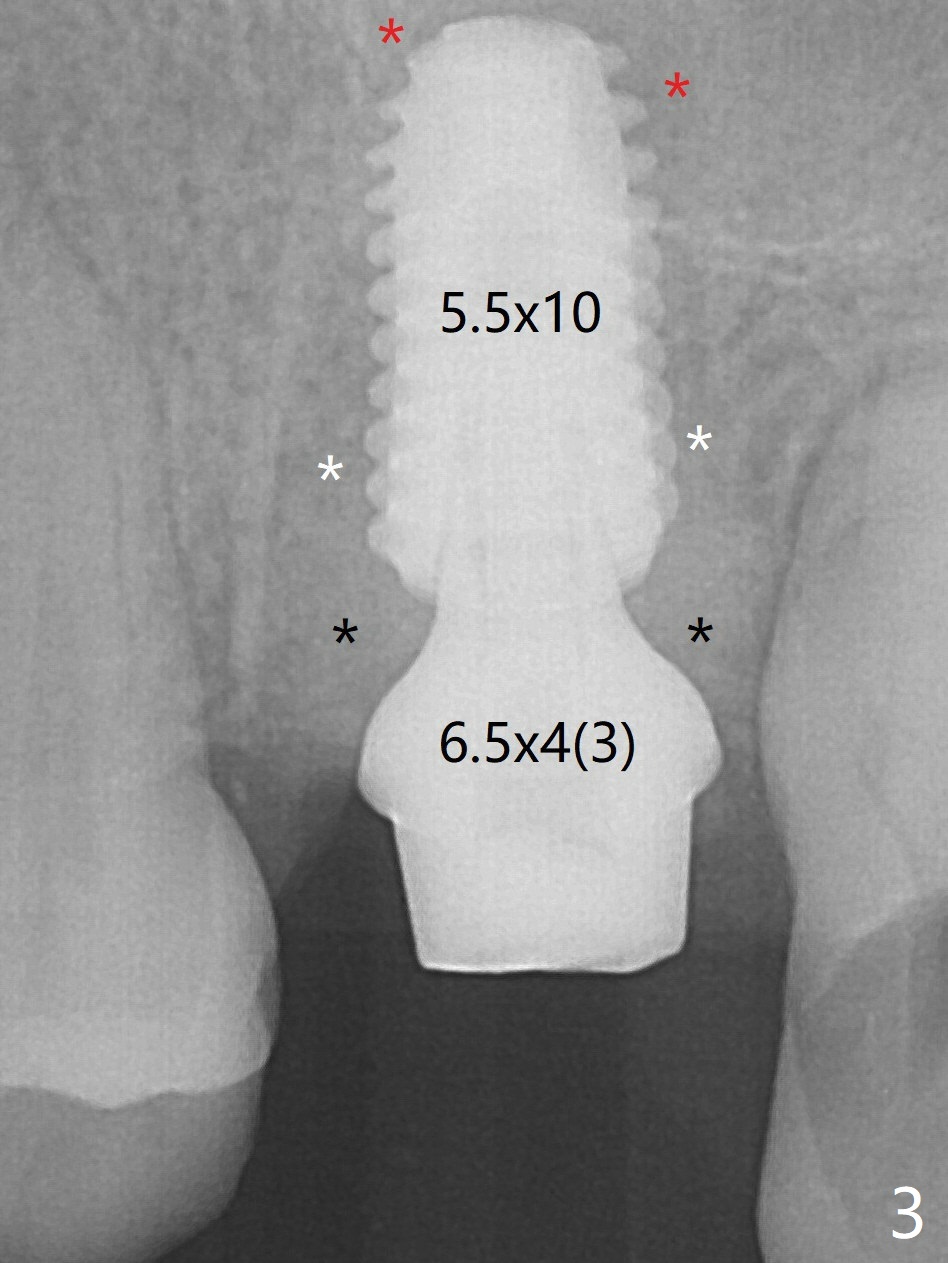

Following sinus lift with Vera Graft with autogenous bone (Fig.3 red *), a 5.5x10 mm implant is placed ~ 1 mm coronal to the septal crest and 1-3 mm apical to the surrounding crest (mesiodistobuccopalatal, >55 Ncm).  After further bone graft around the implant (Fig.3 white *), a 6.5x4(3) mm abutment is inserted with the 3rd round of grafting (Fig.3,4 black *).  An immediate provisional is fabricated to keep the allograft in place.  The implant seems to have osteointegrated 5 months postop (Fig.5).